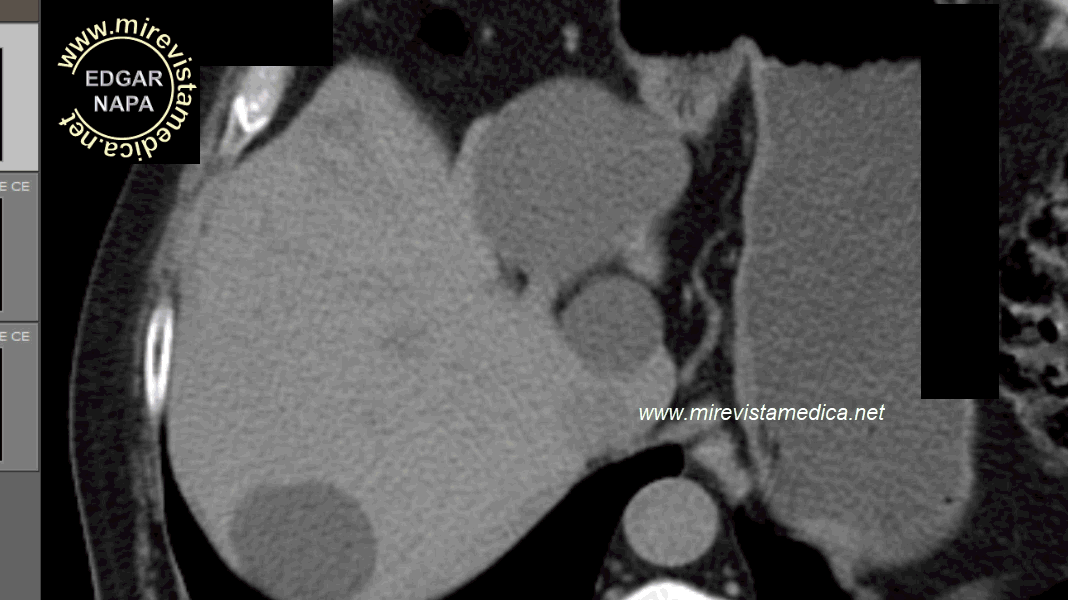

Tomografía abdominal, con contraste , muestra la pared hiperdensa que delimita su silueta.

Tomografía abdominal, con contra ste, muestra imagen hiperdensa en la fosa vesicular. en relació n con vesícula de paredes calcificada.